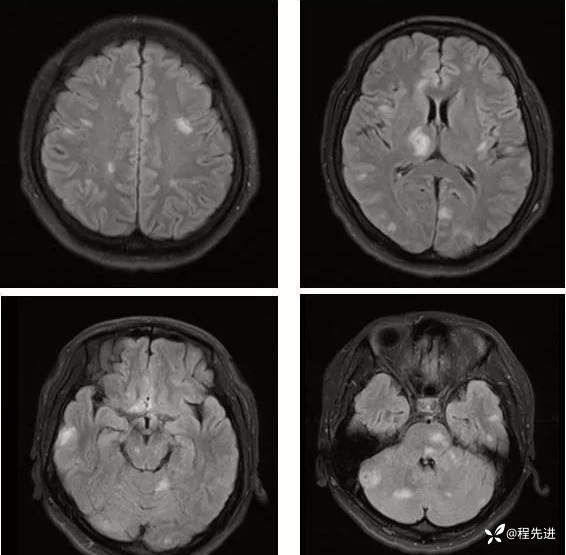

【神经】特别精彩病例|发热、头痛20天

主诉:发热、头痛20天

病史:患者20天前无明显诱因下出现畏寒、发热,热峰39.5℃,热型不规则,不伴咽痛,流涕,感头昏,有头痛,阵发性加剧,伴呕吐,为胃内容物非喷射性。患者在外院查头颅CT示:未提示异常。外院予以“头孢类、退热药”,无明显好转。我院急诊予以“泼尼松,热毒宁"治疗无明显好转

外院胸部CT:两肺弥漫分布结节斑片影,考虑感染